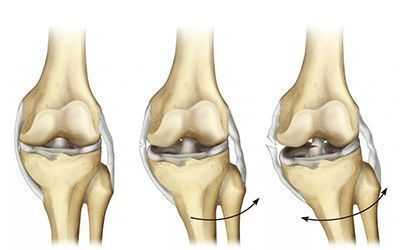

Основным симптомом разрыва крестообразных связок считается симптом «выдвижного ящика».

При помощи специальных приемов врач смещает голень пациента вперед или назад. При разрыве передней крестообразной связки голень избыточно смещается вперед — симптом «переднего выдвижного ящика», а при разрыве задней крестообразной связки голень легко смещается назад — симптом «заднего выдвижного ящика».

При застарелых разрывах связок симптом «выдвижного ящика» может стать нечетким вследствие развития вокруг места разрыва жировой клетчатки, которая отчасти стабилизирует коленный сустав. Диагноз уточняют при МРТ исследовании.

Из-за деструктуризации фронтальной крестовидной связки страдает биомеханика сочленения в целом: возникает нестабильность сустава и патологическое смещение суставных поверхностей относительно друг друга. Это неблагоприятным образом воздействует на хрящевые покрытия взаимодействующих костных единиц - они начинают страдать от нерациональных нагрузок при движениях. Если вовремя не откорректировать связочный аппарат, может развиться гонартроз, который приводит к серьезным дегенерациям не только суставного хряща, но и менисков.